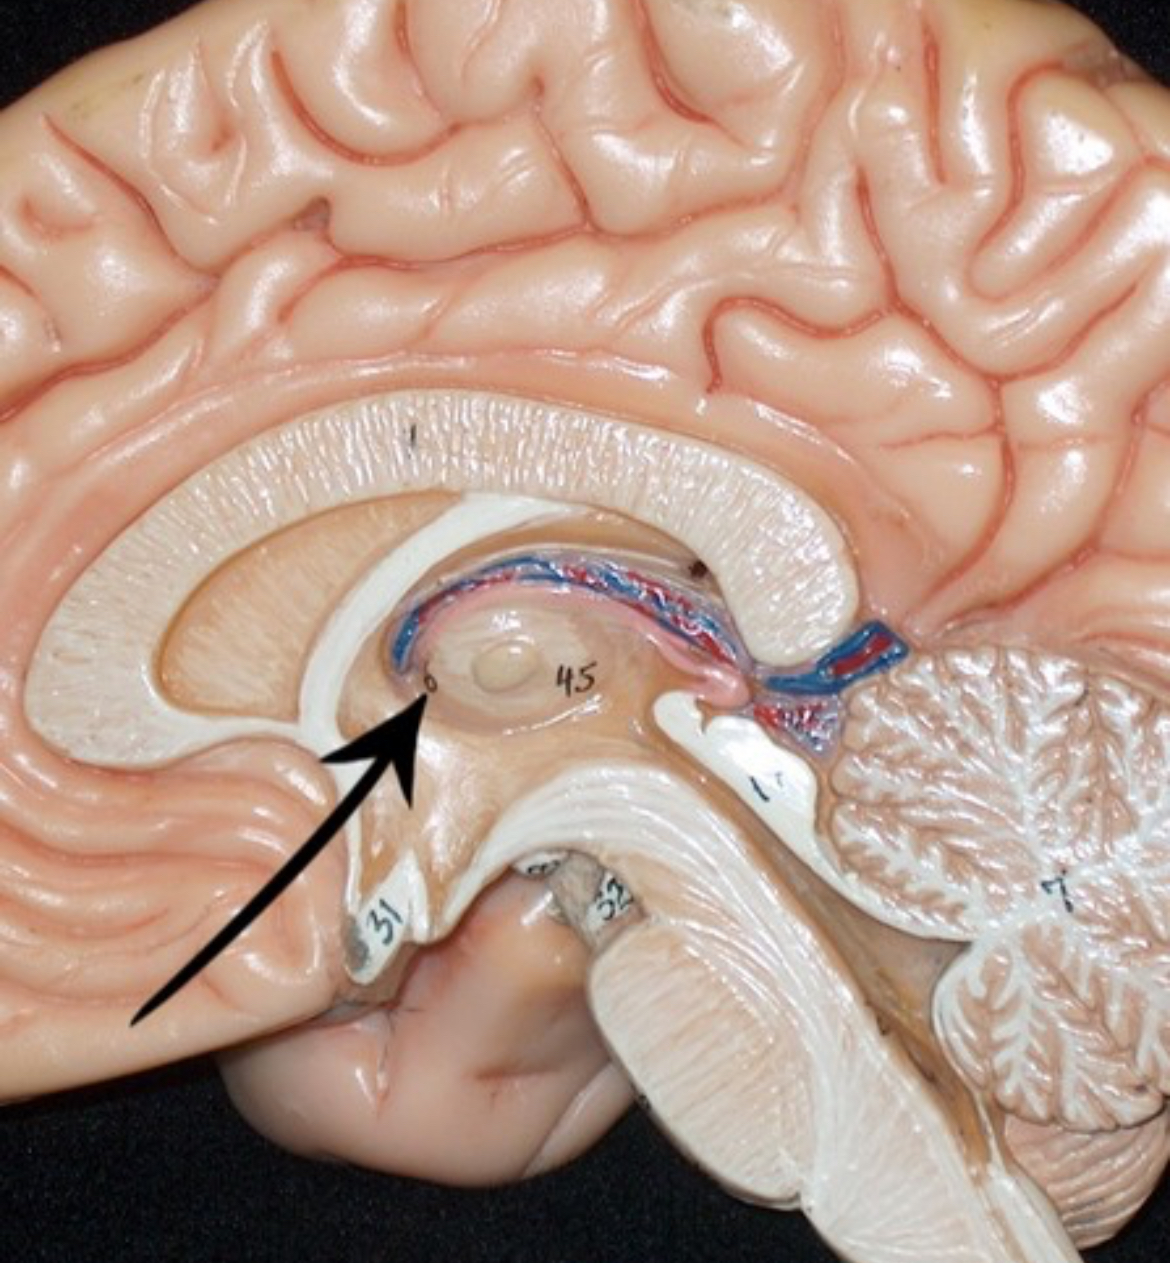

Left lateral ventricle

Right lateral ventricle

Anterior horn of ventricle

Posterior horn of ventricle

Inferior horn of ventricle

Third ventricle

Cerebral aqueduct

Fourth ventricle of stick model

Dural sinuses